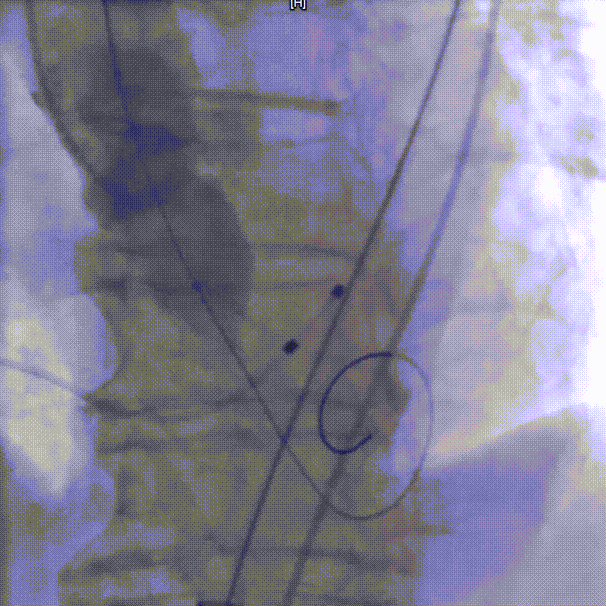

输送器过弓

瓣下3mm定位

左冠窦侧偏深,需回收再定位

回收调整至零位定位,释放到工作位位置合适

完全释放后无反流,冠脉灌注良好